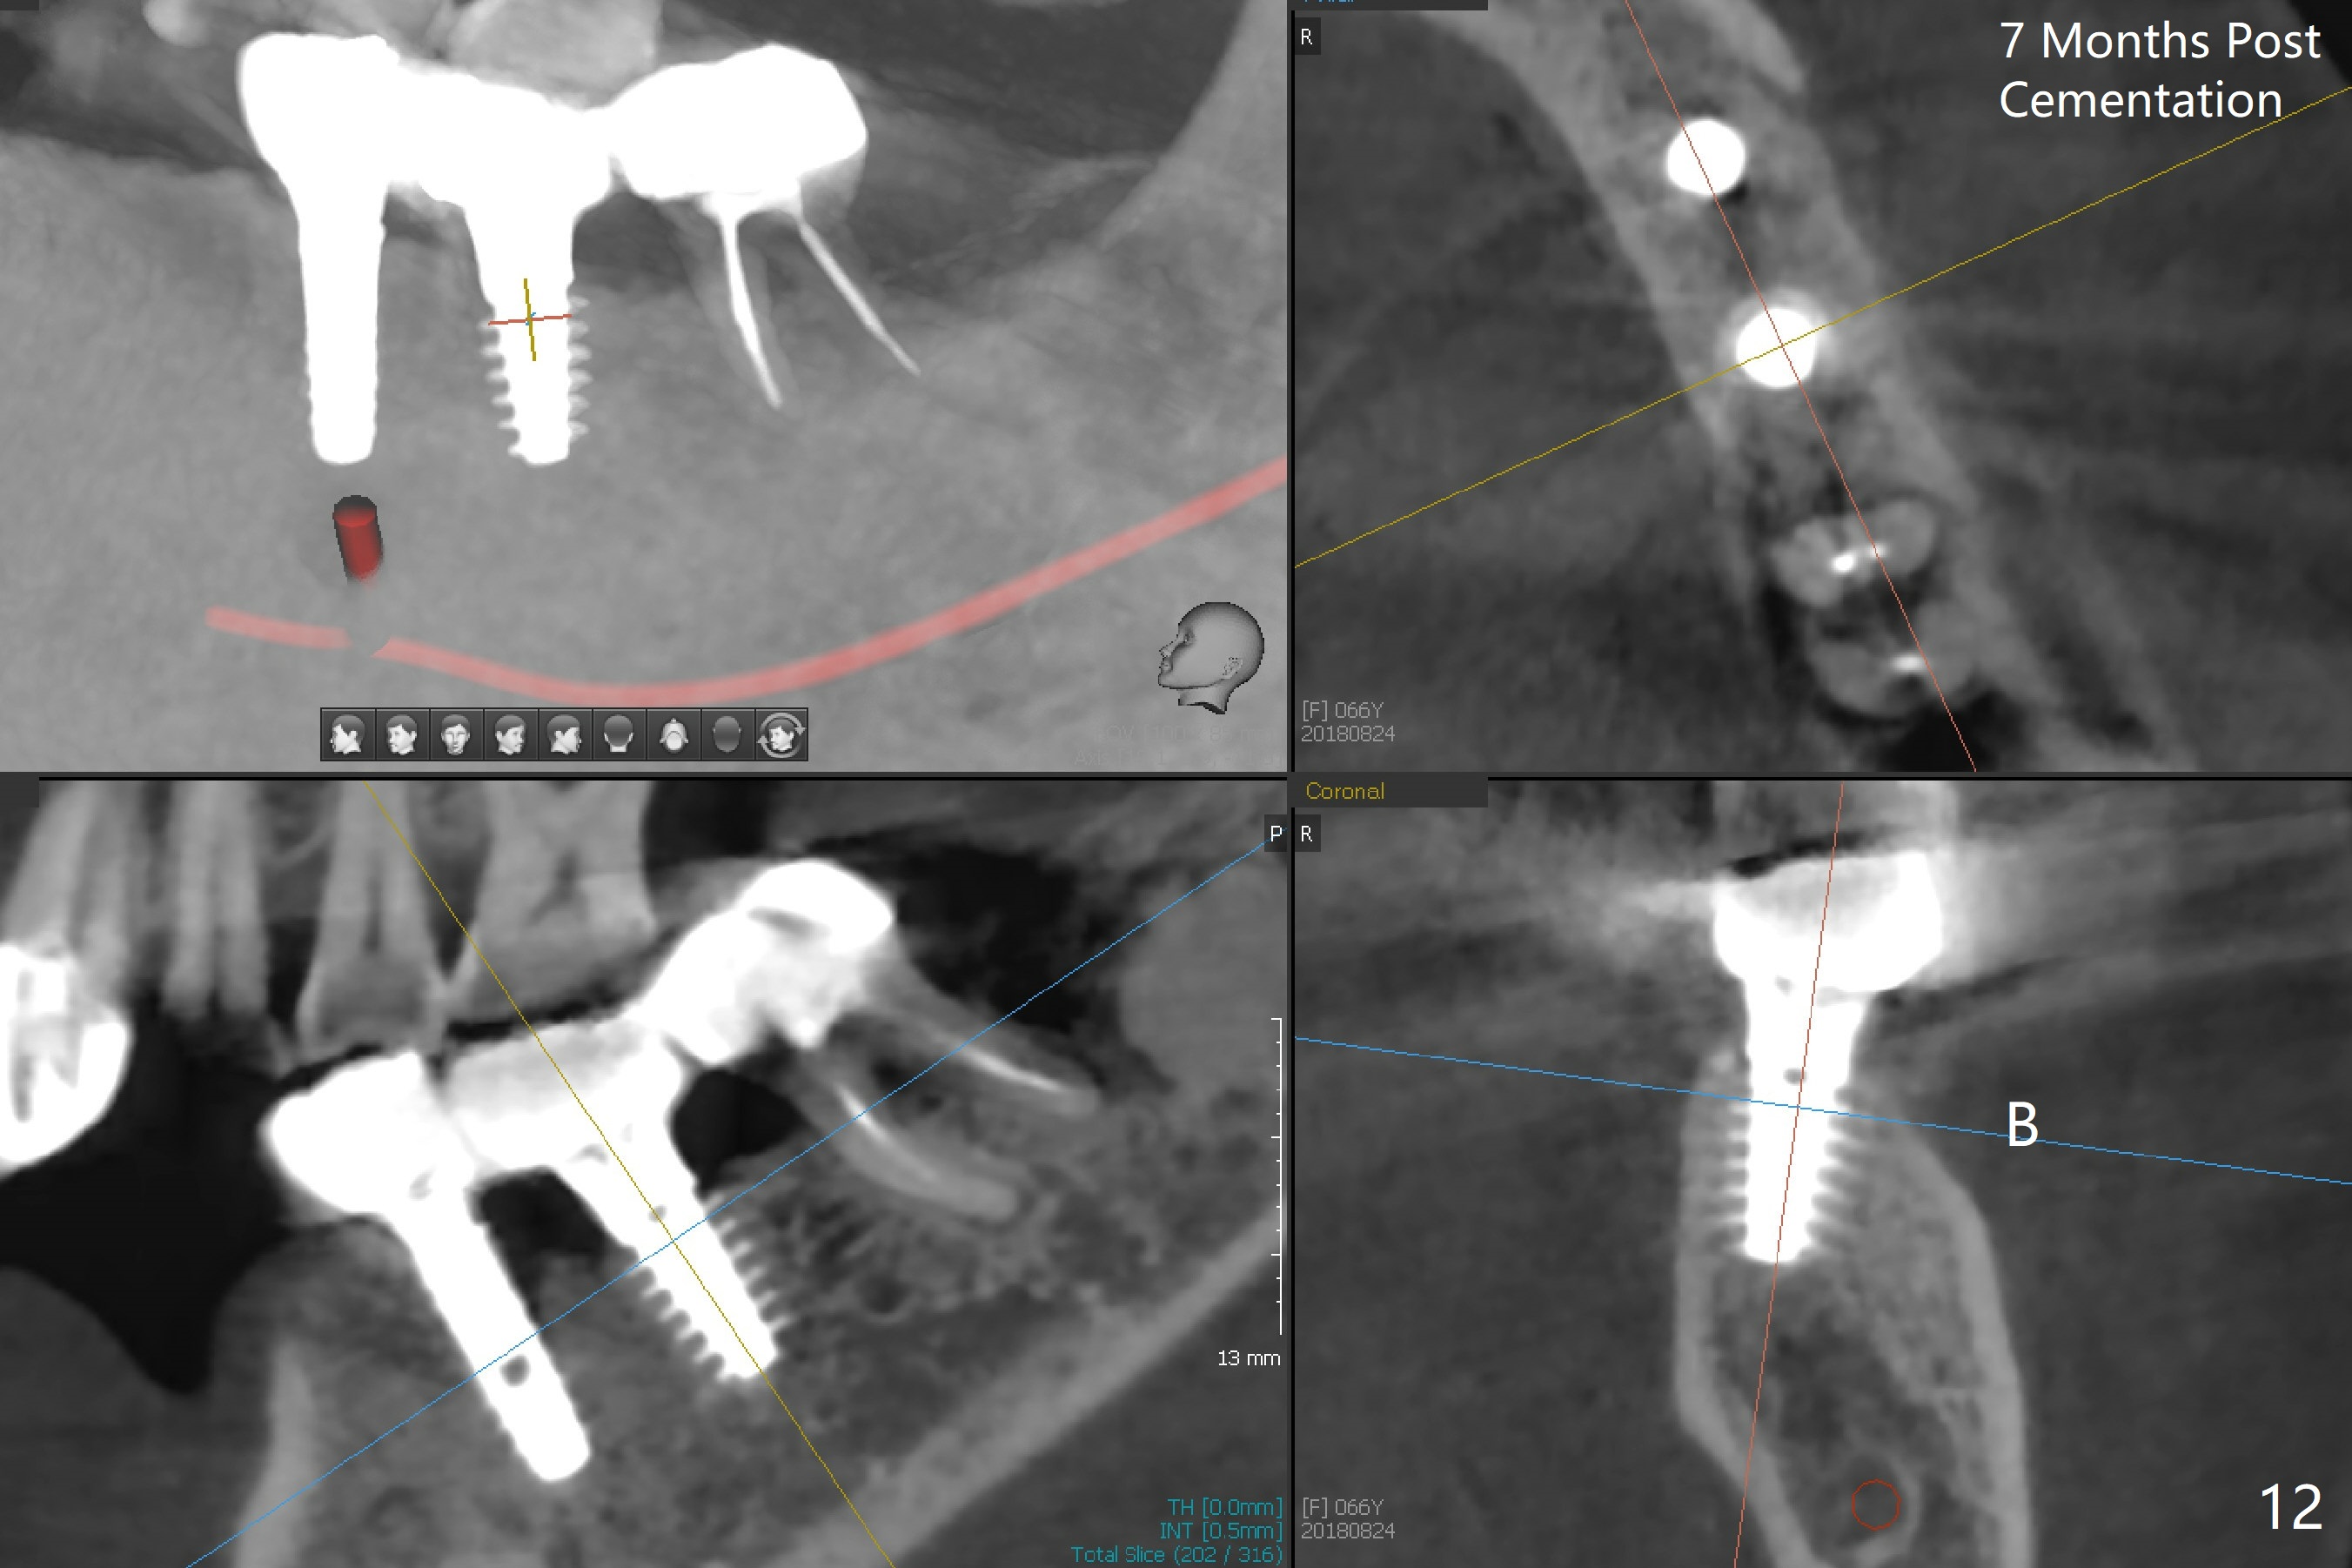

There is no bone loss at #20 or 19 six and 3 months postop, respectively (Fig.6,7). After placing and trimming a 4.3x3 mm Magicore solid abutment, impression is taken (Fig.8). After cementation for #19 and 20 crowns, the crown of #20 is removed for cement removal; attention is paid to cement removal around the crown at #19. In fact, the removal is ineffective with the crown of #20 is reseated and retightened (Fig.9 >). Repeated removal proves to be futile (Fig.10 >). The most effective method will be to take X-ray immediately after #20 crown removal and reseating without torque so that it will be easier to remove the remaining cement if needed. It may be ok in term of hygiene, since proximal brush is used daily. While the crowns at #18 and 19 are being redone because of food impaction, the tooth #18 needs RCT; the Magicore seems to have no bone loss 4 months post cementation (Fig.11). CBCT shows that the Magicore seems to have been placed in the middle of the crest 7 months post cementation (Fig.12 (B: buccal)). The gingiva at #19 is apparently healthy 8 months post cementation. The crown at #19 is recemented 10.5 months post cementation (Fig.13).